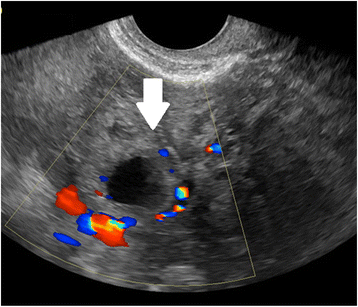

A cervical EP is identified on ultrasound by a distended cervical canal containing a gestational sac with peripheral Doppler flow (Fig. 6), below a closed internal cervical os [102, 103]. The ‘sliding organ’ sign, or movement when pressure is applied with the transvaginal probe, is associated with spontaneous abortions in progress and should be absent in a cervical ectopic pregnancy.

Cervical ectopic pregnancy by transvaginal ultrasound. Doppler shows circumferential flow. The arrow indicates Doppler flow inside the gestational sac, associated with the embryo. Such Doppler flow will not be found in a spontaneous abortion, which may slide down into a similar position at the cervix